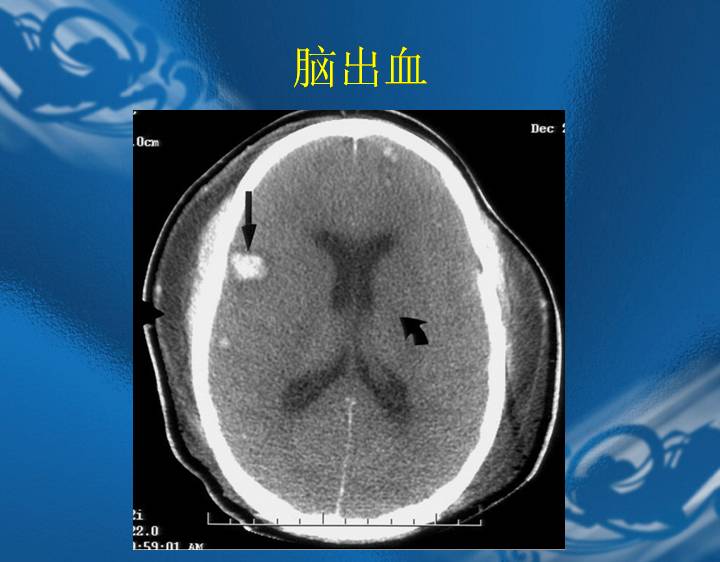

执业医师资格考试“实践技能”影像学辅导资料